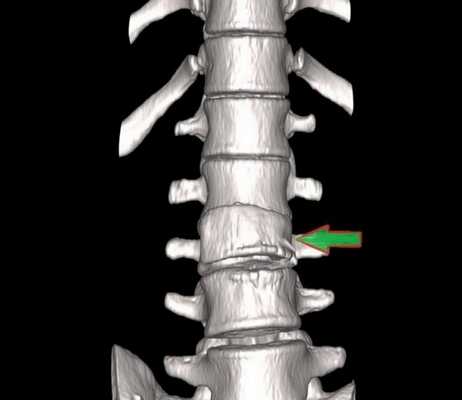

Компрессионный перелом (показан стрелкой) поясничного отдела позвоночника